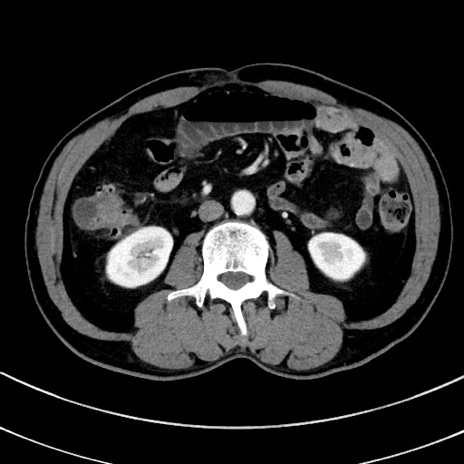

冠状断像

【症例】 60歳代男性

【主訴】 黒色吐物

【現病歴】 4日前から嘔気自覚、2日前の朝食後にも嘔気あり、自分で手で嘔吐反射起こし嘔吐したところ血が混ざっていたため受診。

【既往歴】 5年前汎発性腹膜炎を伴う急性虫垂炎で手術、高血圧、前立腺肥大症、高脂血症

【身体所見】 腹部正中に手術癩痕あり 腹部平坦・軟圧痛なし膨満感あり

【データ】WBC 8400、CRP 4.54